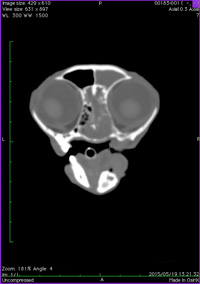

猫の鼻腔腺癌